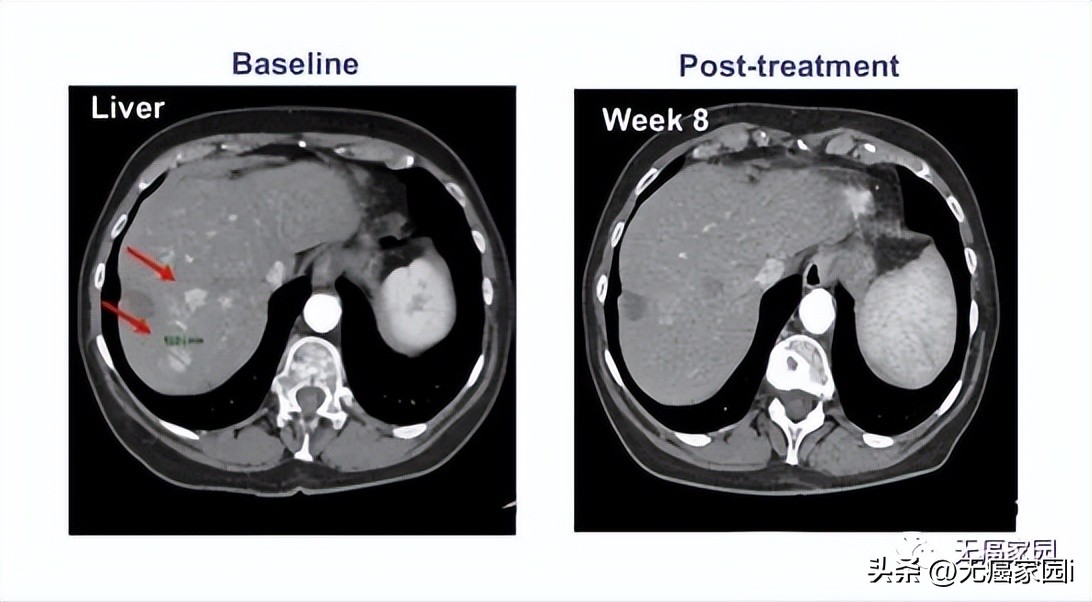

参与的9例患者均接受过手术及常规放化疗,但出现失败或不耐受的现象。在接受最高剂量治疗的4例患者中, 有1例患者获得完全缓解,CT扫描显示,患者体内所有病变都消失了,而且完全缓解后已持续半年以上无任何复发的状态!

其他患者(队列1、队列2)最佳反应是病情稳定。队列2中的1例患者 在治疗1个月后原发病灶体积未缩小,但纵膈淋巴结转移灶体积明显缩小!